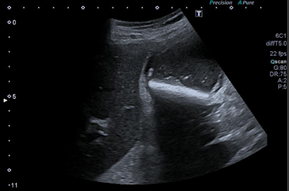

Exploramos con sonda convex en corte longitudinal en epigastrio una imagen ovalada de predominio anecoico de bordes bien delimitados que en corte transverso se extiende longitudinalmente por la linea media de forma ovalada y de diametro mayor a 93,3 mm que presenta contenido hipoecoico en semiluna adherido a pared altamente sugerente de aneurisma aortico con trombo endomural que en algunas zonas ocupa más del 50% de la luz del vaso.